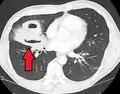

| Computed tomography (CT) scan of chest showing bilateral pneumonia with abscesses, effusions, and caverns. 37-year-old male. | |

Lung abscesses are often on one side and single involving posterior segments of the upper lobes and the apical segments of the lower lobes as these areas are gravity dependent when lying down. Presence of air-fluid levels implies rupture into the bronchial tree or rarely growth of gas forming organism.